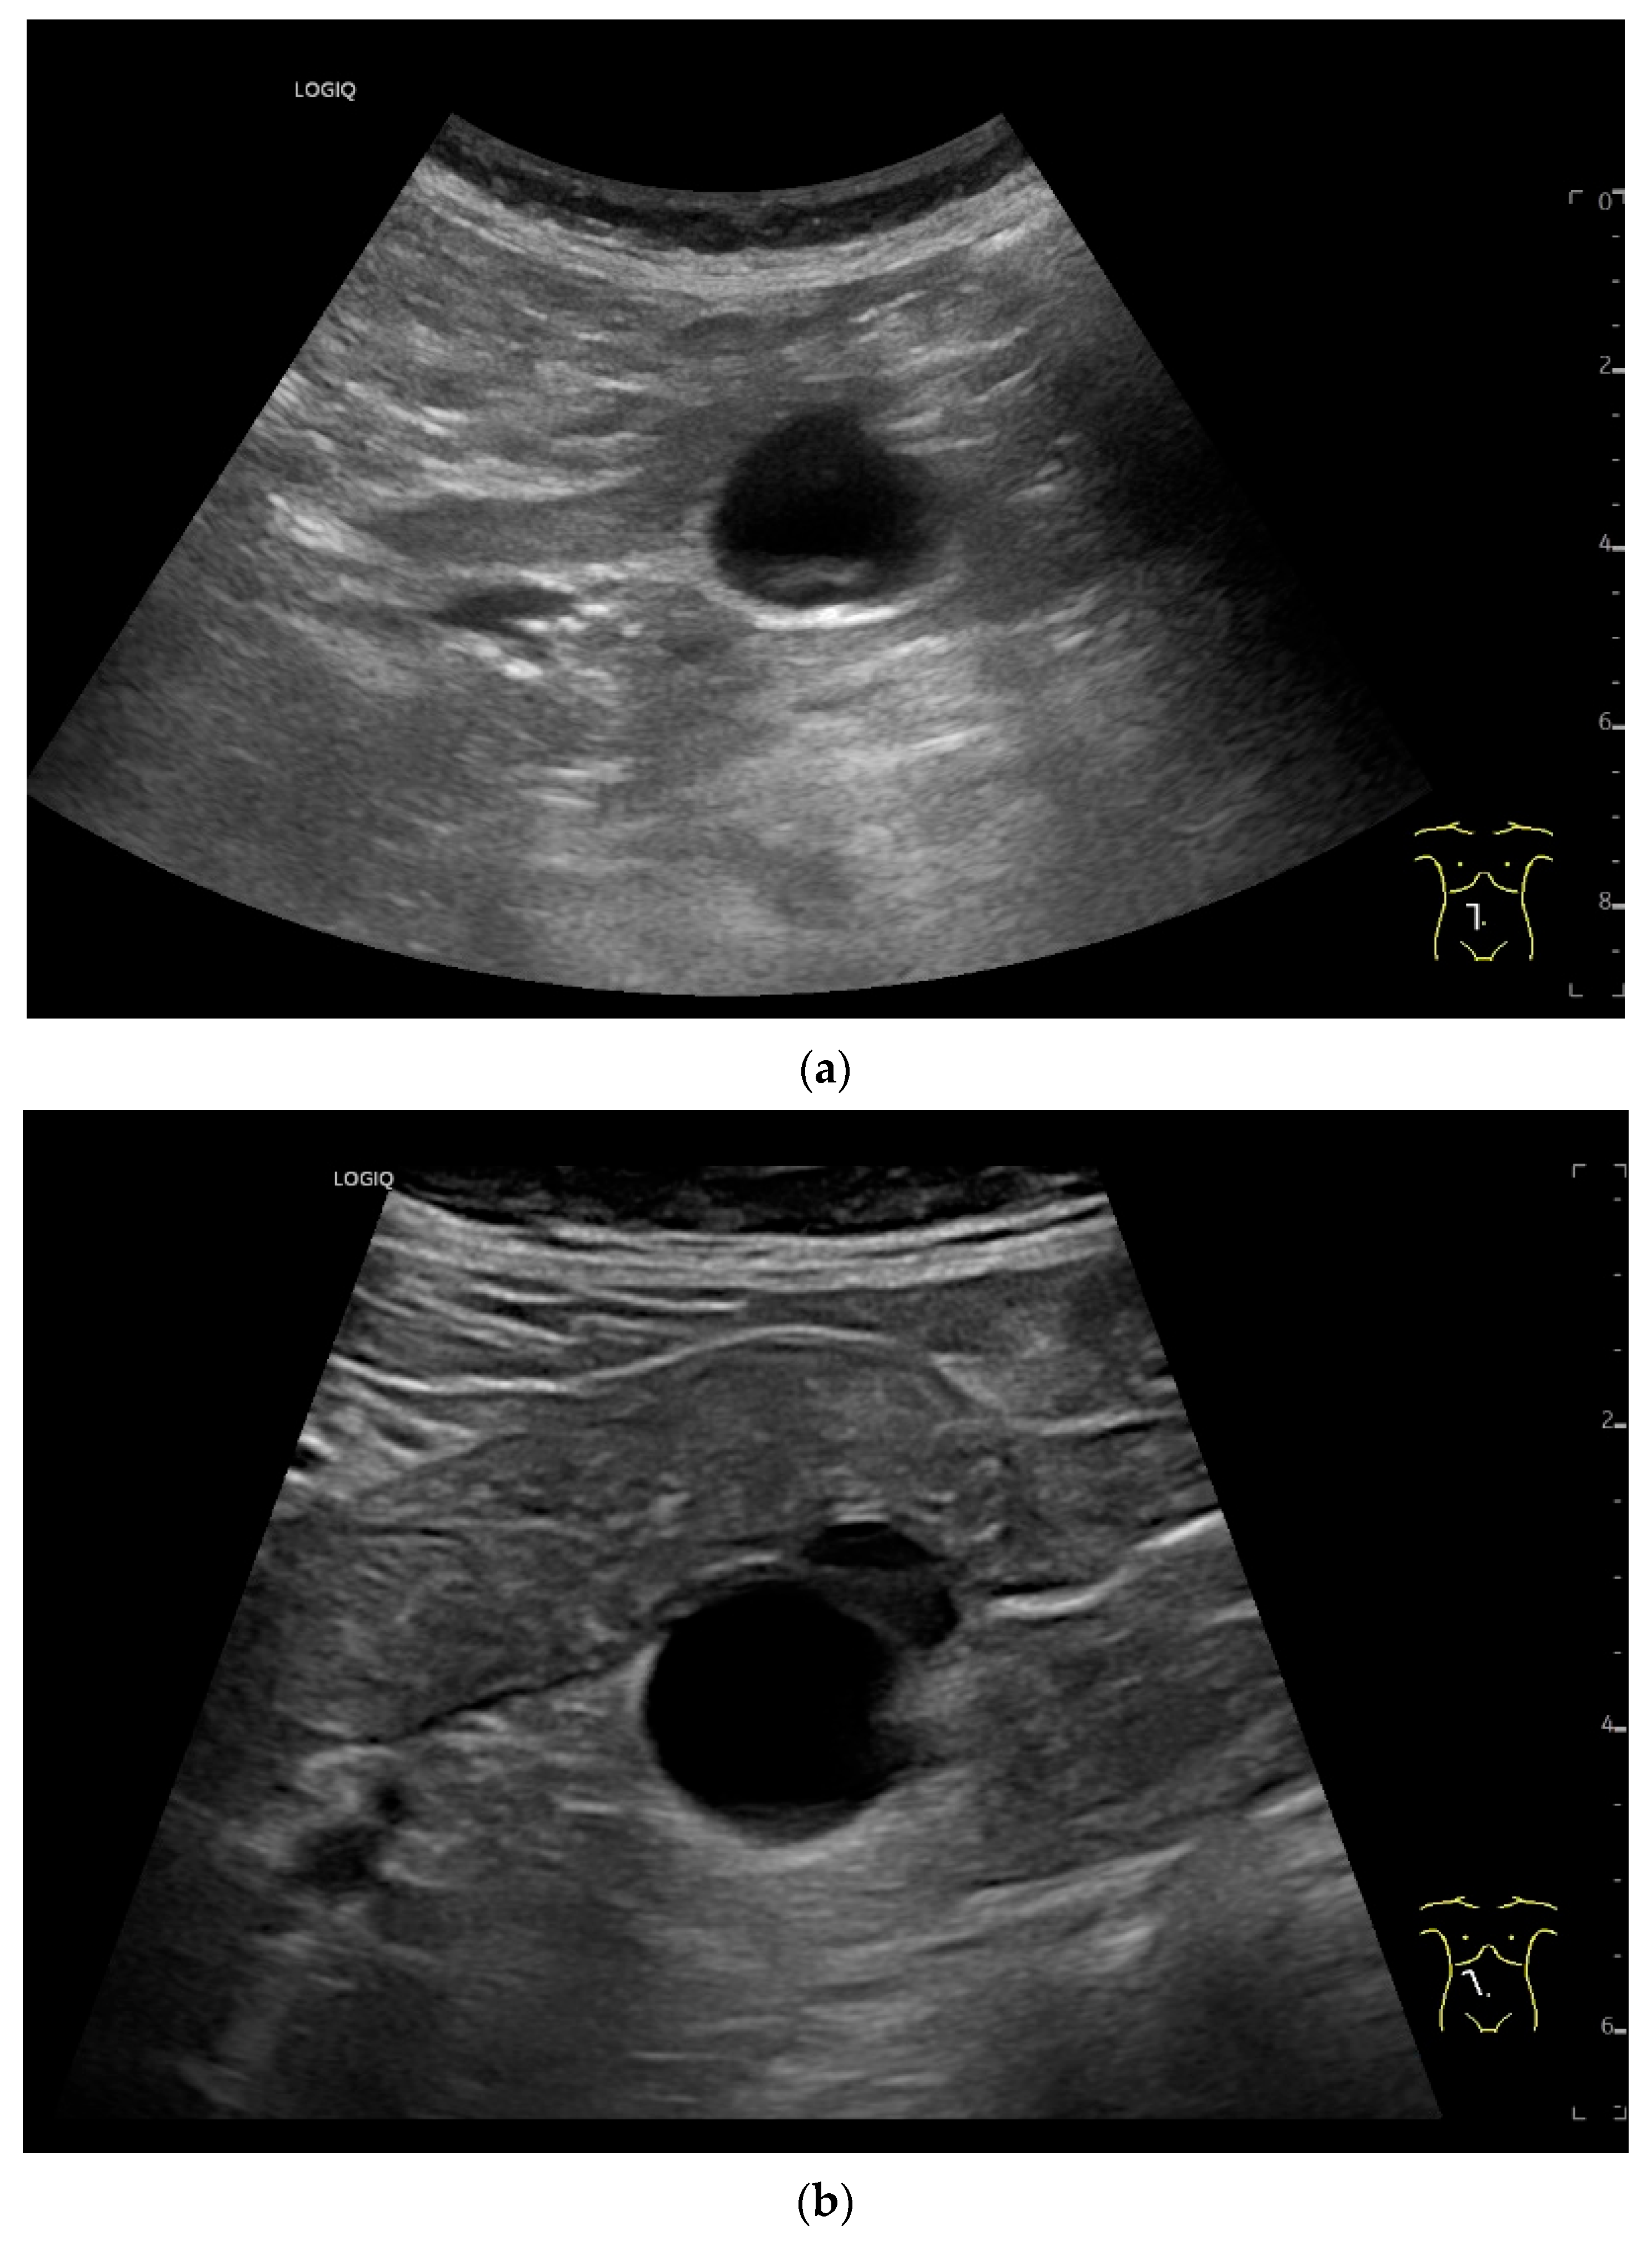

Lymphangiomas are very rare benign tumors of the gastrointestinal tract and can occur in the intestine, the gall bladder and the pancreas [3]. However, they are more likely to be vascular malformations that are filled with lymph. Lymphangiomas consist of different sized spaces that contain lymph. They exist in three variants: capillary, cavernous and cystic variants [134]. Children are usually affected. However, lymphangiomas can also be diagnosed in adulthood if they cause intussusception or other acute obstructive symptoms due to the increase in size [135,136,137]. However, as with other intestinal tumors, lymphangioma can manifest with gastrointestinal bleeding. US can be used to detect and localize the most anechoic lesions and determine their cystic appearance [134,135] (Figure 15). On CT, the tumors appear as homogeneous, non-enhancing lesions with variable attenuation values depending on whether the fluid is chylous or serous [134].

Figure 15.

Cyst related to the serosa of the Jejunum. An incidental finding reveals a smoothly defined, non-echoic lesion in the right mid-abdomen using the abdominal sector transducer (a). Using the linear transducer, the cystic lesion can be visualized adjacent to the small intestine/jejunum (b). Kerckring folds are visible. The cystic lesion moves with the jejunum. The lesion is in contact with the small intestine wall (between the markers) (c). In CEUS with 2.0 mL SonoVue (linear transducer 9 MHz), the wall shows subtle enhancement. The lesion itself shows no enhancement and is therefore not solid, but liquid. The wall of the adjacent small intestine shows clear enhancement (d). Differential diagnoses include lymphangioma or mesothelial cyst. Since the elderly patient was completely symptom-free and showed no signs of gastrointestinal bleeding, no surgery was performed. The findings remained on follow-up.